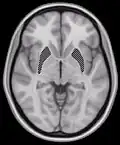

This is a transverse section of the striatum from a structural MR image. The striatum includes the caudate nucleus (top) and putamen (right) and the globus pallidus (left).